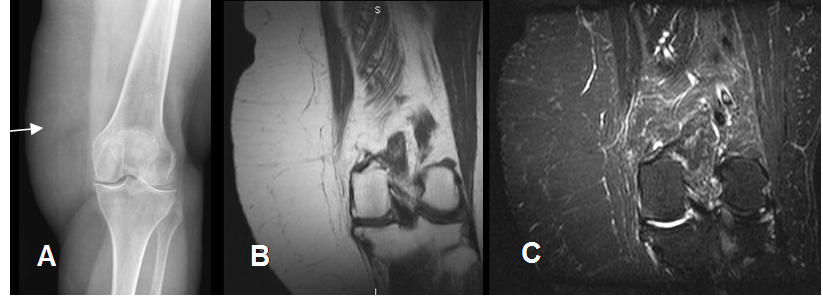

Fig 163 A. Lipoma.

A: Rx AP y B: RM coronal en T1 y C: RM coronal en STIR. Gran prominencia en los tejidos blandos de la parte lateral de la rodilla, por tejido graso que corresponde a lipoma no encapsulado.